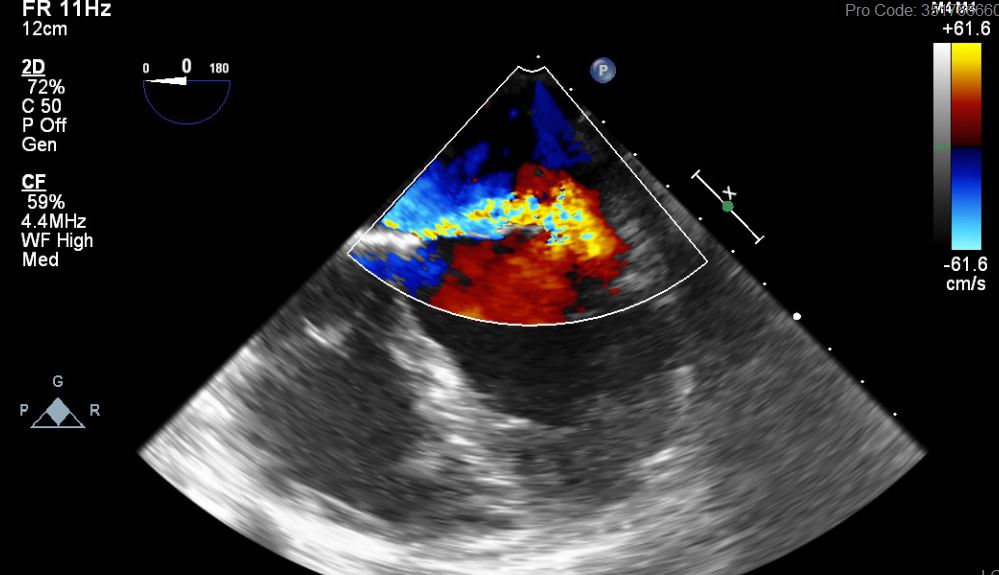

What's the Diagnosis?